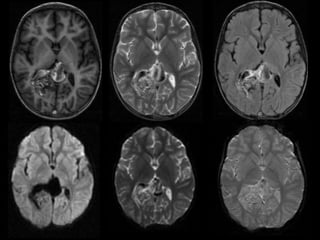

RMN DE CRÁNEO

20/06/2023

ADQUISICIÓN AXIAL

T1 T2 FLAIR

DWI ADC EG

ADQUISICIÓN AXIAL.

T1 CC

ANGIO TOF

3D

 Malformación arterio-venosa cerebral con

dilatación aneurismática de la vena de galeno vs

aneurisma de la vena de galeno vs fístula

arteriovenosa pial. Escala de Spetzler – Martin 5

puntos.

Hallazgos en RM

Potenciación en T1

o VPM: vacíos de flujo o imagen heterogénea por flujo

rápido o turbulento.

o Artefacto de fase por flujo rápido y turbulento.

o Focos hiperintensos en el interior del cerebro: Ca++,

isquemia.

Potenciación en T2

o VPM: vacío de flujo o imagen heterogénea por flujo

o Vacíos de flujo de las arterias nutricias en torno al

VPM.

o Los focos isquémicos no se visualizan bien en el

cerebro infantil sin mielinizar.